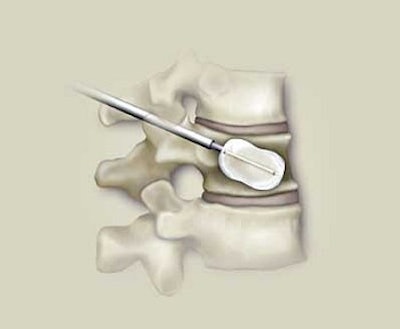

![]() |

A vertebral compression fracture causing pain and spinal deformity (above). Below, a biopsy needle is guided into the fractured vertebra through a small incision in the skin. Inset shows a magnified view of the interior of the osteoporotic vertebra with the needle in place.